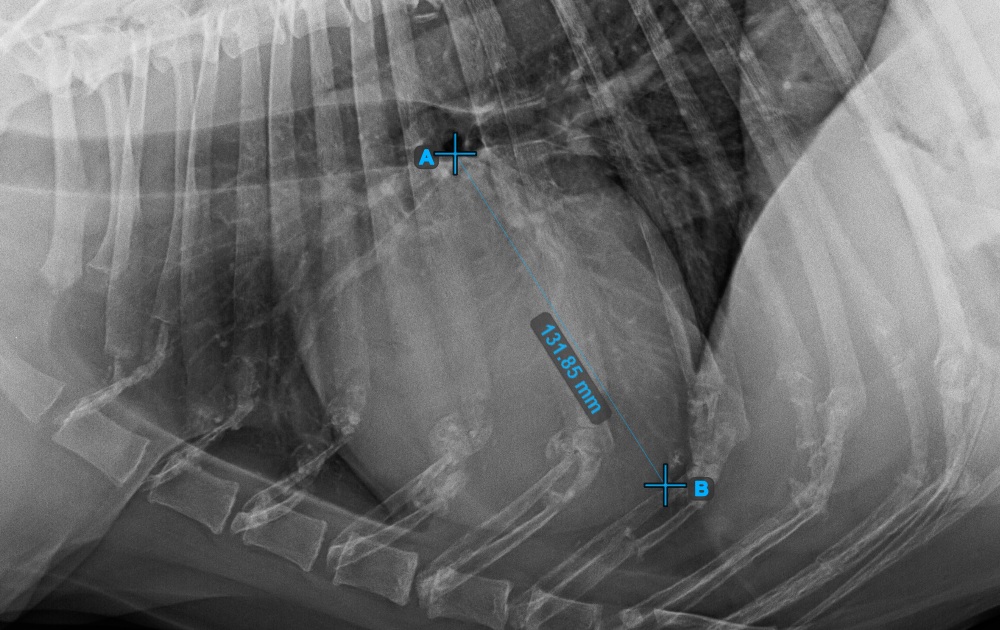

Start the measurement by marking the Bifurcatio tracheae, near the top of the heart.

The image below represents a typical placement of the Bifurcatio tracheae point.

../../_images/image393.jpg